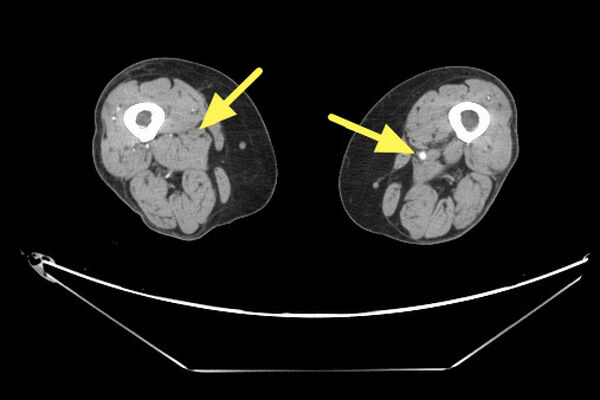

楊凱迪醫師近期診治一名64歲長期洗腎的女性患者,數月來反覆出現下肢刺痛,夜深與洗腎後特別明顯,同時右小腿與腳踝各有一處約3x5公分久未癒合的慢性傷口。整形外科醫師清創時發現傷口幾乎沒有出血,轉介心臟血管外科,經「踝臂血壓指數(ABI)檢查」左右腳分別為僅約0.67及0.64,代表下肢血流循環不良。電腦斷層血管攝影更顯示雙側股動脈及膕動脈嚴重狹窄。

▲右股動脈脈阻塞(左側箭號處)。(圖/聯新國際醫院提供)